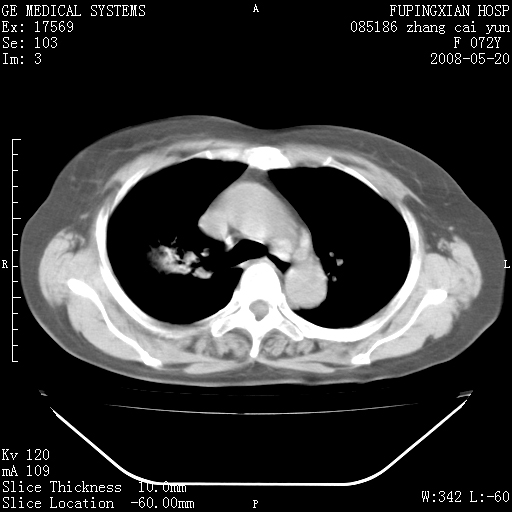

标题: CT13542:发热,咳嗽数日,经抗菌素治疗好转,请大家看排除 [打印本页]

标题: CT13542:发热,咳嗽数日,经抗菌素治疗好转,请大家看排除

右上叶支气管走行自然,未见明显管壁增厚等征像,另左主支气管起始部可见异常腔道向左侧延展左肺动脉干后方,与左下叶支气管相通,为左下叶支气管变异?

有节段性阻塞性肺炎与不张,近段支气管狭窄,周围散在肿大淋巴结影,以周围型肺癌可能性大,建议纤支镜检查。

右肺上叶实变影,内见支气管充气征,右上叶支气管通畅,肺门区未见软组织密度影,抗炎治疗有效,考虑炎症,建议继续抗炎治疗复查。

右肺阻塞性肺炎  不除外支气管内膜结核

考虑为:右肺上叶感染性病变。建议:1)继续抗炎治疗后复查。2)必要时行纤支镜检查。